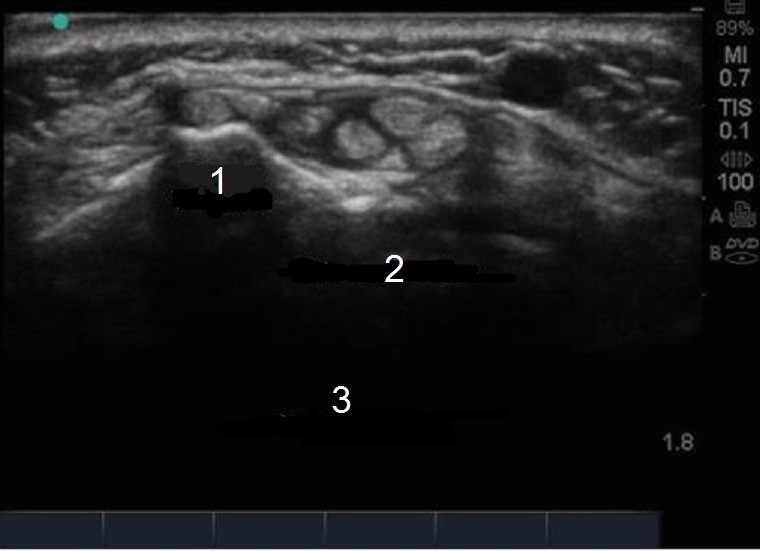

Wrist Extensor Tendon Image

Lister's Tubercle

Extensor Tendon

Compartment 2